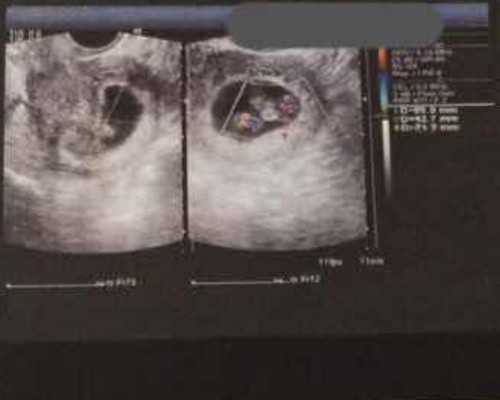

供卵试管依靠第三方卵子,主要针对更年期或者卵子质量有严重问题的女性。郑州大学第一附属医院可以做第一代、第二代、第三代试管。至于供卵,现在还不清楚。如果这家医院能做出供卵,成本大概就是试管成本减去降促排成本,如下。

1.前期检查:这个费用大概是3000-5000元。检查项目包括:血型、血常规、乙肝丙肝检查、梅毒筛查、艾滋病筛查、染色体筛查、宫颈癌筛查、卵巢功能检查等。

2.降级:这个费用大概是1000元-20000元;

3.促排卵和取卵:最近一周开始促排卵和促排卵药物。有进口药和国产药,有不同的方案。使用时间不同,大致在2-4万左右;

4.胚胎培养:胚胎分为新鲜囊胚和冷冻胚胎。一般3天后囊胚培养4天。费用略贵,5000-10000元左右;

5.移植:因为医院可以做第一代、第二代、第三代试管,所以试管的费用是不一样的。第一代试管婴儿费用约1万元,第二代试管婴儿技术费用约2万元,第三代试管婴儿技术费用约4万元。

无论年轻女性还是老年女性,在郑达一附院生殖科做供卵试管都不确定。我们能知道的是供卵的国产成本其实就是试管成本。当然供卵借助别人的卵子,一般是冷冻卵子,没必要促排卵取卵。患者也会省去很多痛苦和时间,费用大概在3-10万元。虽然郑大一附院生殖科做供卵是个未知数,但是这家医院的试管技术还是挺不错的,有第一代、第二代、第三代试管需求可以详细咨询。